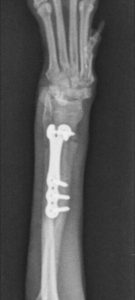

În cazul raselor de talie foarte mică, cunoscute drept “toy breeds”, fracturile de radius și ulnă constituie o categorie aparte de traumatisme ortopedice. Vascularizația redusă la acest nivel face ca aceste oase să fie vulnerabile chiar și în urma unor accidente minore – o săritură din brațele proprietarului sau de pe mobilier poate fi suficientă pentru a produce o fractură completă.

Tratamentul acestor leziuni este delicat, deoarece diametrul osos este extrem de redus, iar stabilizarea trebuie realizată cu maximă precizie. În prezent, dispunem de implanturi ortopedice de ultimă generație, concepute special pentru pacienții sub 2 kg, care permit stabilizarea sigură și eficientă a oricărui tip de fractură.

Pentru aceste rase, un pas esențial în managementul postoperator îl reprezintă extragerea implanturilor după confirmarea radiologică a vindecării osoase. Eliminarea acestora reduce riscul de resorbție osoasă și contribuie la menținerea unei integrității structurale optime pe termen lung.

Intervențiile sunt realizate cu anestezie inhalatorie și tehnici de blocaj loco-regional, ceea ce diminuează semnificativ nivelul de durere resimțită de pacient atât în timpul intervenției, cât și postoperator.

Astfel de situații demonstrează cât de mult contează echipamentele adecvate, experiența echipei și un protocol bine stabilit pentru a obține o recuperare completă și sigură.